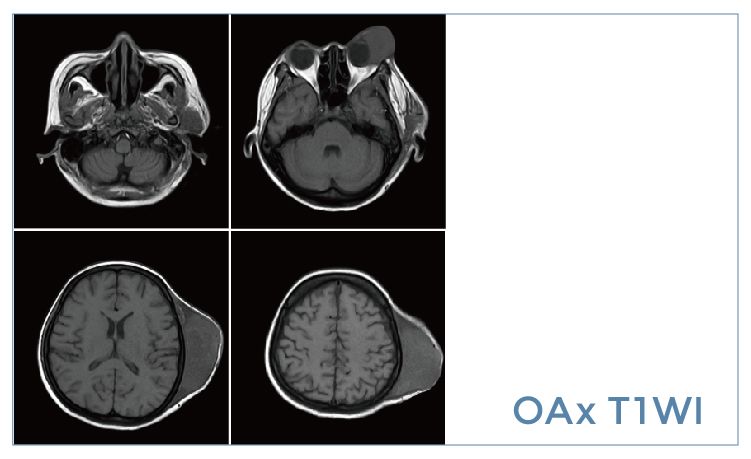

【朗润影像档案】磁共振影像病例分享(编号20190920)